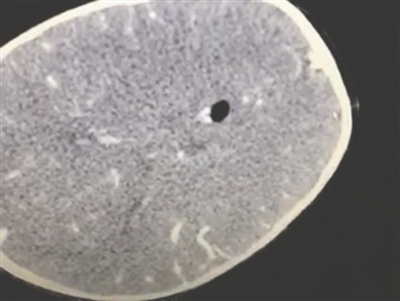

开颅手术 取出筷子视力明显恢复

“经 过检查,筷子是从孩子的右侧眼眶进入脑内病深入对侧。不幸中的万幸是,筷子进入颅内时,避开了眼球以及大的血管。”主刀的神经外科司马秀田医生介绍,好在 孩子送医和手术都比较及时,手术持续了4个小时左右,医生对小林受损的脑组织、硬膜进行了清创与修复。幸运的是孩子视力有明显恢复,神经系统也没有明显的 损伤。

“这类手术最怕的就是感染。”司马秀田说,插入颅内的筷子10~15厘米长,刚用过的筷子是污染的,孩子送来的时候在发烧、白细胞比较高,而目前来看,孩子烧退了,且白细胞也正常了,说明孩子基本度过术后的感染关。